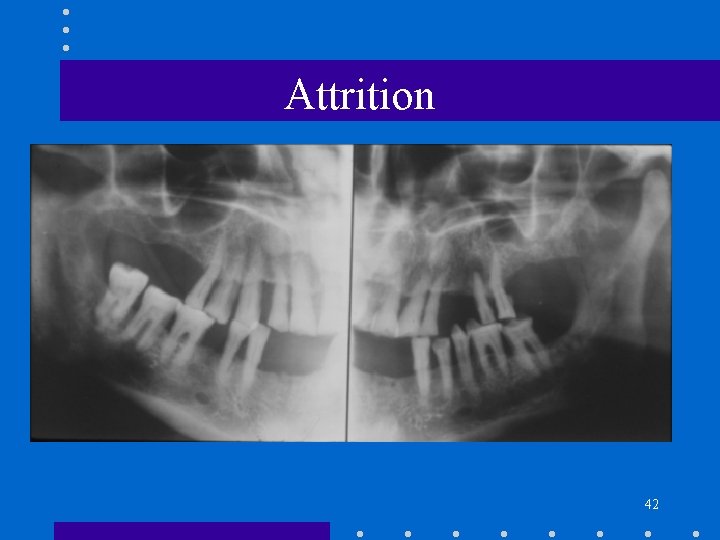

Regressive Alterations • Attrition • Abrasion • Erosion 38

Attrition • • Physiologic wearing away Incisal, occlusal and interproximal surfaces Part of aging process Bruxism – pathologic attrition 39

Attrition – Radiologic Features • • • Change in normal outline Flat occlusal plane Loss of mamelon Pulp chamber, canal size Hypercementosis 40

Attrition 41

Attrition 42